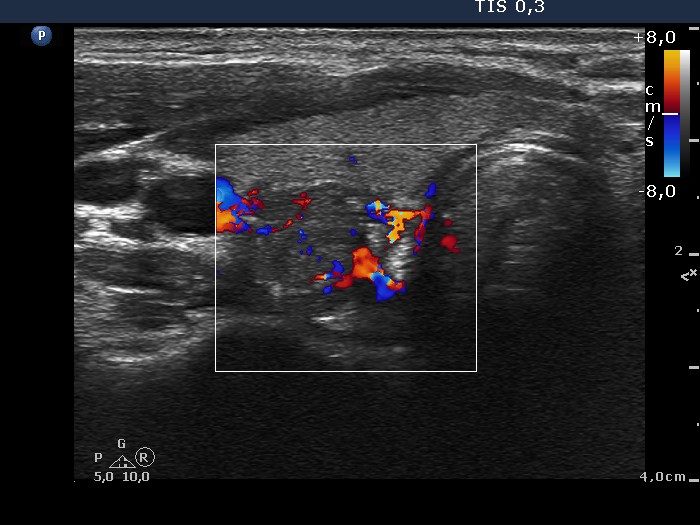

Lymph nodes - case conp 058 (ultrasonographic picture 6)

Lower part of the right lobe, transverse scan, color Doppler mode. This nodule presents irrregularly increased intranodular vascular pattern.